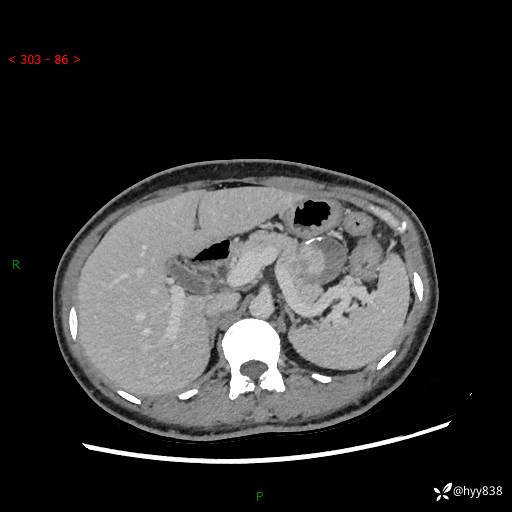

增强动脉期+静脉期

img